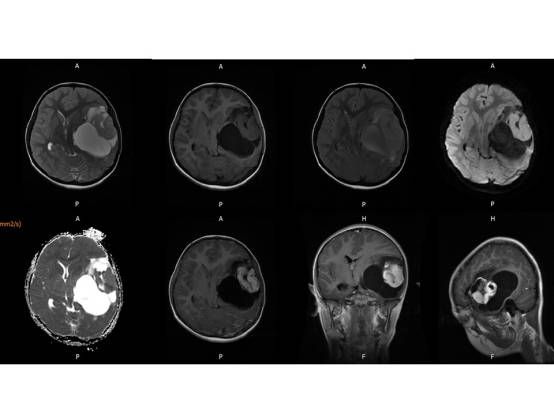

MR平扫及增强示:

左侧颞叶见大块状等长T1等长T2异常信号,FLAIR呈高新,DWI(b=1000)实质部分呈稍高信号,ADC实质部分呈等信号,边界尚清,周围脑实质受压。注入GD-DTPA后病变实质部分呈明显强化。

(左颞)血管周细胞瘤WHO II级。